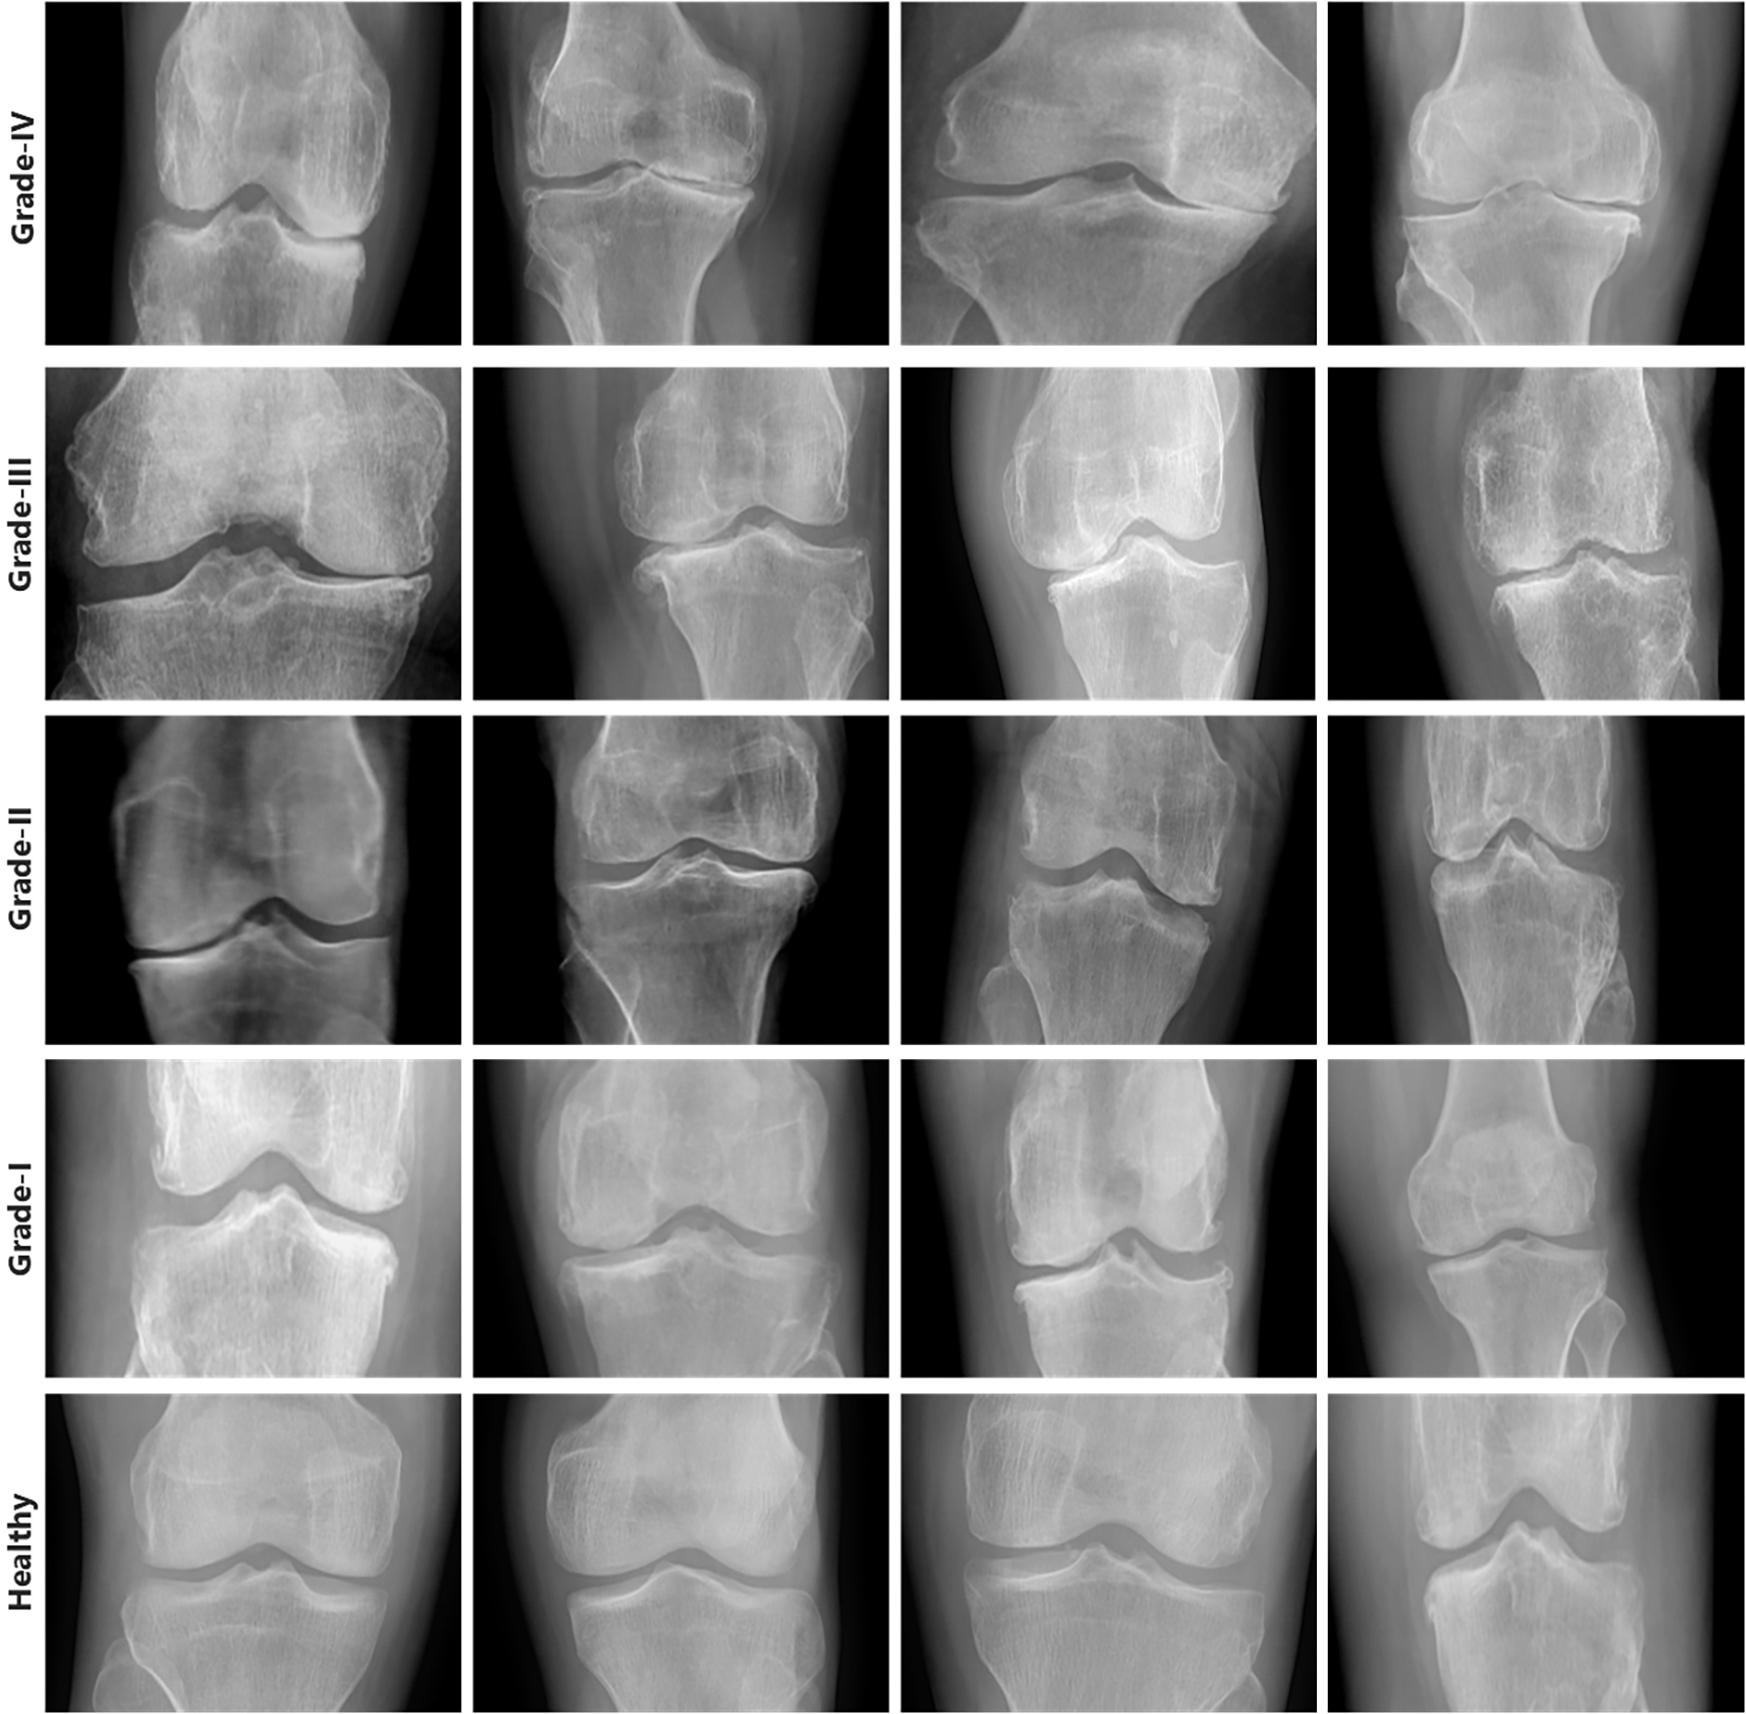

First, we collected two datasets such as Mendeley Data V1 and OAI [24] for training and cross-validation respectively. We performed various experiments using these two datasets. Mendeley dataset contains about 2000 knee X-ray images having dimensions 224 × 224 × 3. For the OAI dataset, the Multicenter Osteoarthritis Study (MOST) [25,26] and Baltimore Longitudinal Study of Aging (BLSA) [27] conducted a longitudinal, prospective, and observational study of 4,796 people. The categorization in both datasets was made by a radiologist based on the KL [28] measure, which rates the severity of KOA from 0 to 4. Although each patient’s clinical data may be uniquely recognized by an ID, and the medical pictures come from both legs, it is not possible to link them together and follow the patient’s personal information. Additionally, every patient’s privacy was respected. Some sample images from Mendeley data VI are shown in Fig. 3 exhibiting the various grades and healthy. Knees OST [25,26] and BLSA [27] conducted a longitudinal, prospective, and observational study of 4,796 people that looked at KOA.

Figure 3: Samples from Mendeley dataset

Here, we go into great depth on the dataset that was utilized for training and testing. Mendeley Data V1 [19] is frequently used for KOA severity identification and categorization using the KL grading scale. Mendeley dataset contains about 2000 knee X-ray images having dimensions 224 × 224 × 3. Two medical professionals have annotated knee images for evaluation to categorize them using the KL grading system. In addition, the pictures were in PNG format and grayscale. The dataset was split into training and validation sets in proportions of 70% and 30%, respectively. More specifically, the model was tested on more than 600 knee photos after being trained on over 1400 knee images. Table 3 reports the Mendeley dataset’s features. We considered Expert-I grading for the distribution of datasets, including 456 healthy class images, 370 grade-I images, 195 grade-II images, 182 grade-III images, and 197 grade-IV images. Fig. 8 displays some examples from the dataset.